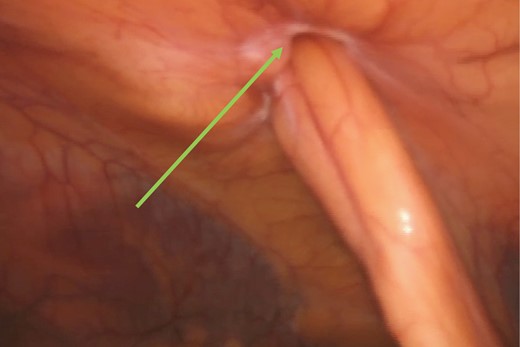

The hernia was repaired laparoscopically through a TAPP mesh repair. Laparoscopic visualization revealed a small umbilical hernia as well as a falciform ligament port site hernia (Fig. 7). The falciform ligament was mobilized and the hernia was reduced into the abdominal cavity (Fig. 8). The peritoneum around the hernia neck was mobilized to clearly expose the neck. The neck was then closed intra-corporeally with an intra-operative V-loc non-absorbable suture™ (Fig. 9). The hernia defect was then covered with an underlay Ventralite™ mesh and secured with Absorbatac™ staples (Fig. 10). The umbilical hernia was not repaired as we had not obtained consent for its repair. This was an intra-operative diagnosis. Her post-operative recovery was uneventful and she was discharged home the same day.

Reduced falciform ligament hernia (green arrow) and left lobe of the liver (orange arrow).